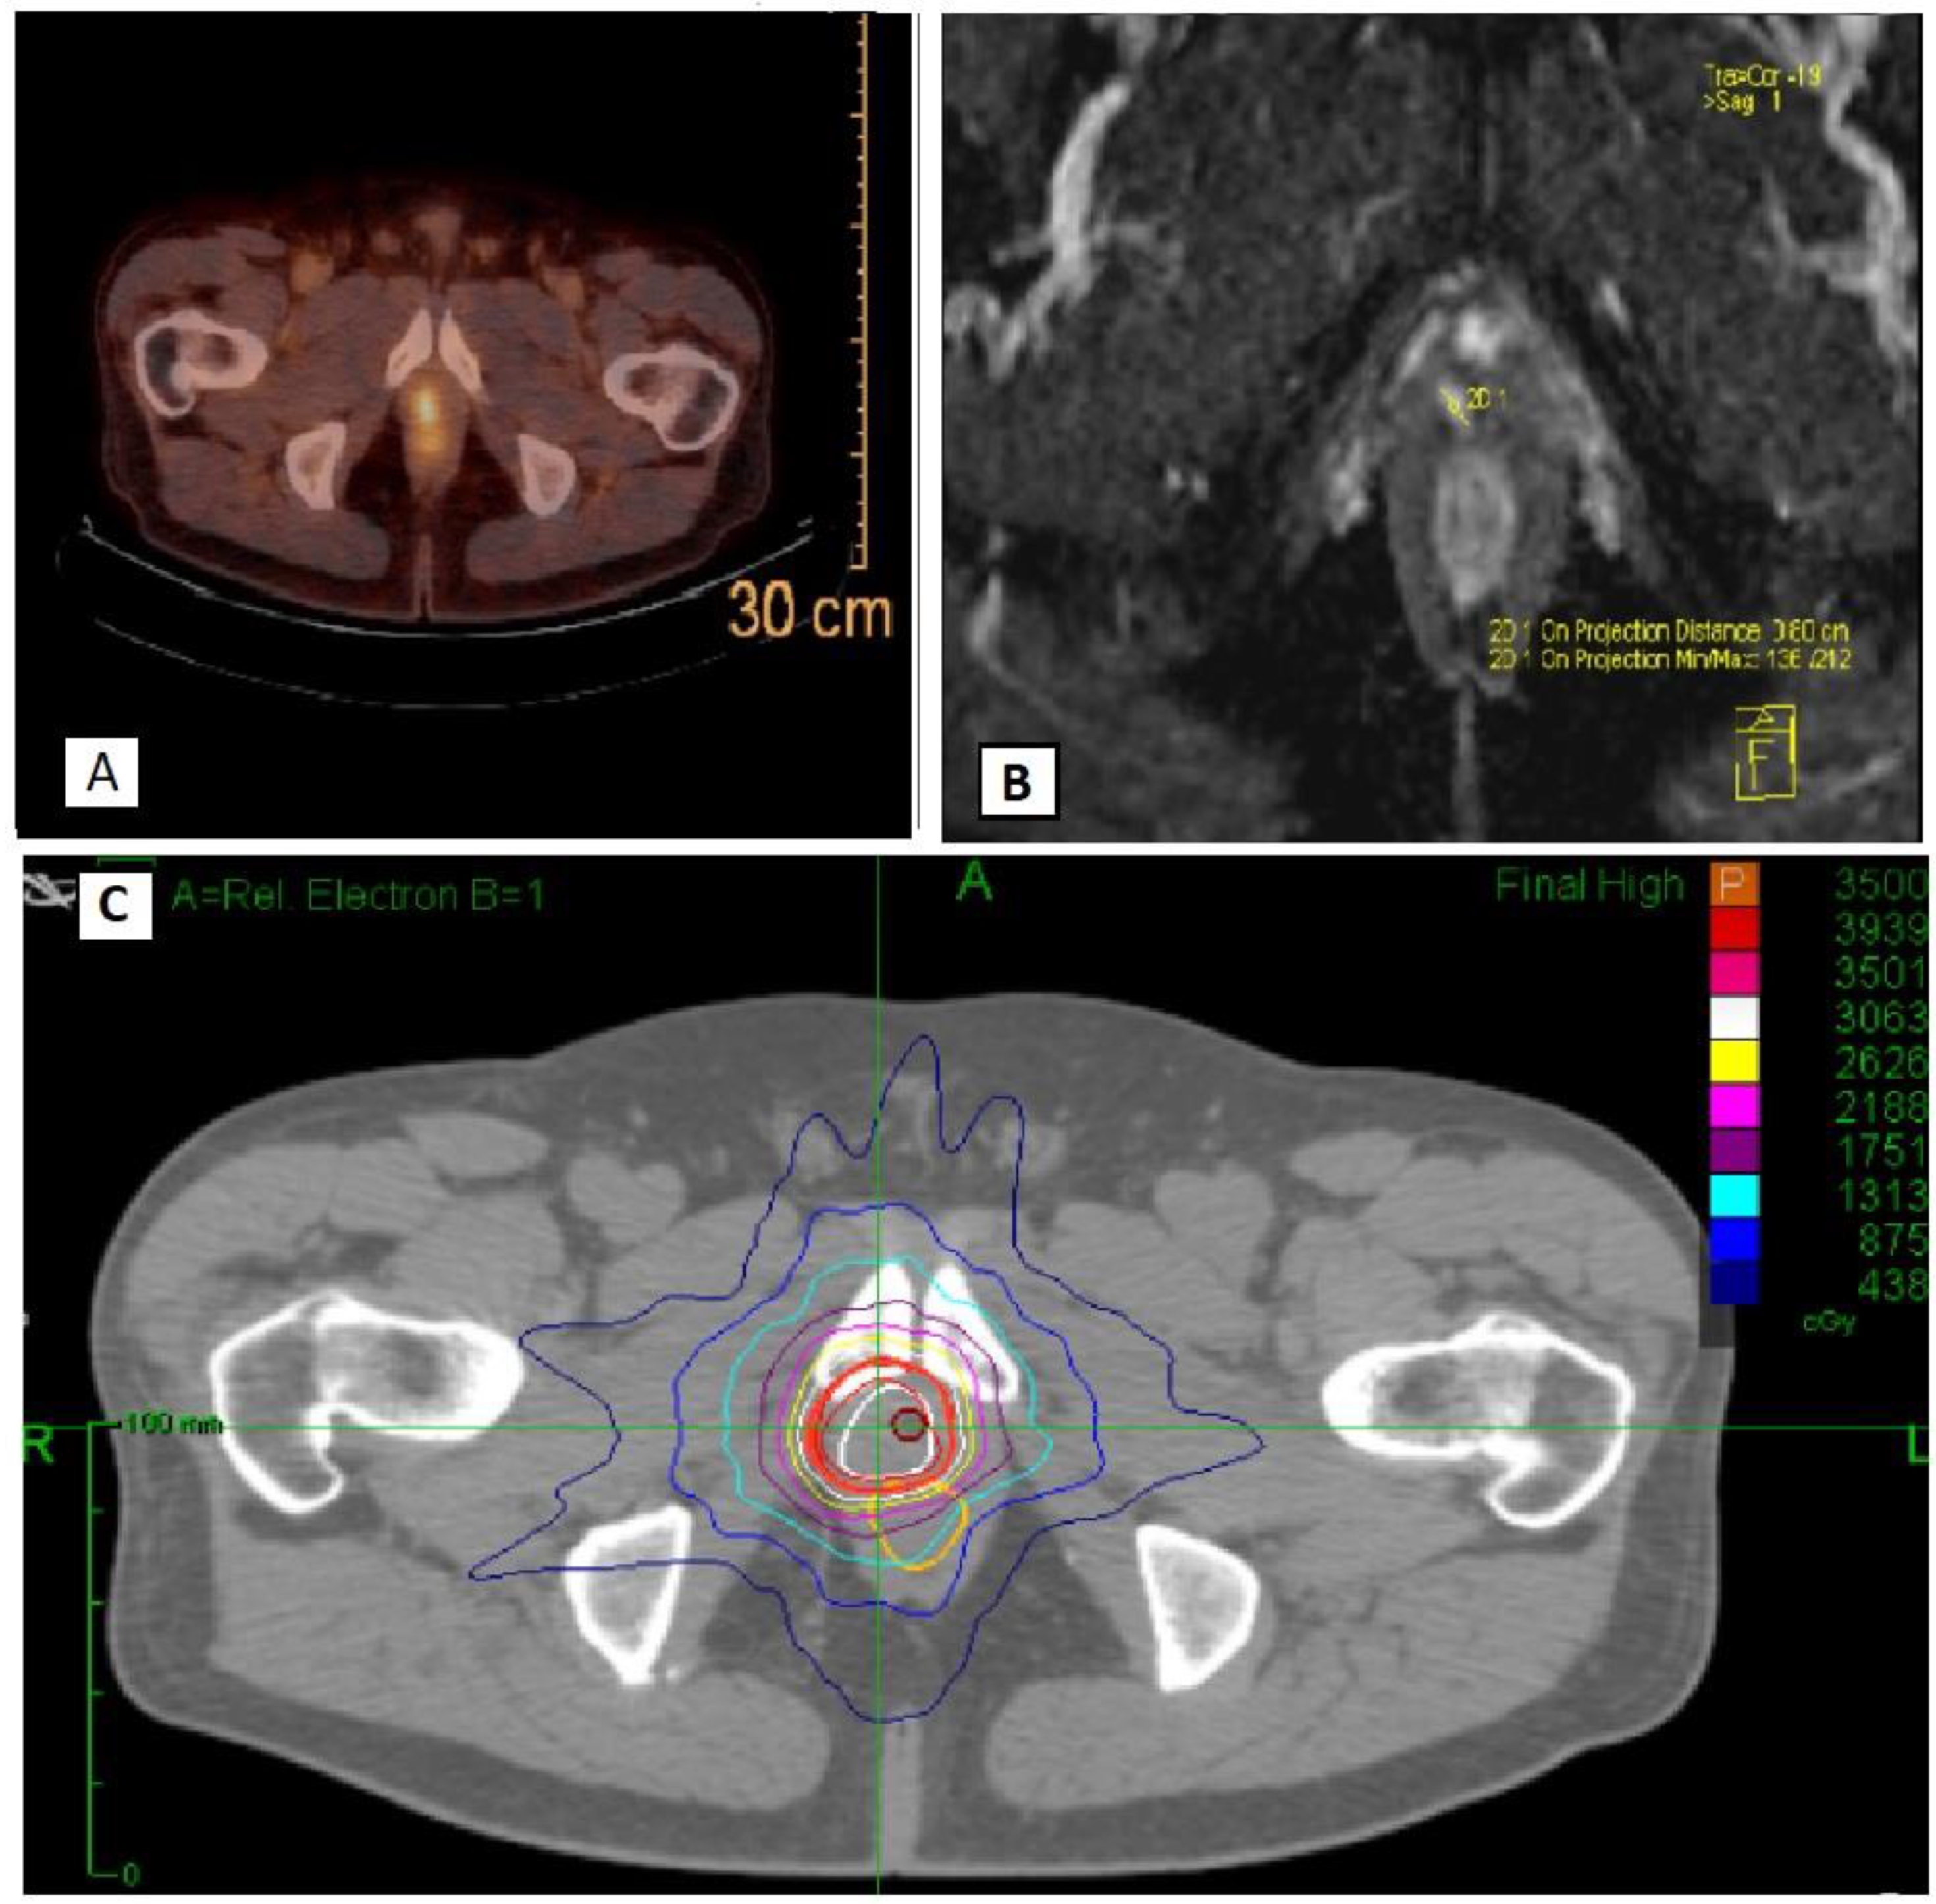

All patients underwent CyberknifeR SSRT for a total dose of 35 Gy in 5 fractions. Treatment was administered with an every-other-day schedule. Use of different techniques (e.g., Volumetric Modulated Arc Therapy-VMAT or MR based SSRT) was allowed within the protocol, provided that the treatment respected doses and fractionation indicated per protocol (35 Gy in 5 fractions) and that dose constraints to organs at risk were observed. However, first, patients were enrolled in the promoting institution, where CyberknifeR SSRT is used for this kind of treatment. PSMA or choline CT-PET and MRI were co-registered with the planning CT scan for target volume delineation purposes. The Gross Target Volume (GTV) corresponded to macroscopic neoplastic tissue within the prostate bed. Clinical Target Volume (CTV) was obtained, adding a 2 mm margin to GTV. A margin of 3 mm (1 mm in the posterior direction) was added to CTV to obtain the final Planning Target Volume (PTV) (Figure 1). Patient alignment and target tracking were performed through implanted fiducials. During delivery, radiographic images were acquired using the InTempoTM System (AccurayInc.), which alters imaging frequency between 15 and 60 s depending on the magnitude of the prostate or recurrence on prostatic bed motion detected. Bladder catheter placement was not performed for planning and delivery procedures. The following organs at risk were contoured: rectum, bladder, bowel, urethra, penile bulb, femoral heads, and bowel. The main dose constraints used are reported in Table 1. Concomitant Androgen Deprivation Therapy (ADT) was not allowed (patients should be free from ADT from at least 12 months before enrollment). All patients were evaluated every three months with a PSA and a clinical examination. The first treatment response evaluation was performed at 3 months after end of treatment with serum PSA. No protocol assessments were performed before 3 months from end of treatment. Re-staging was performed in case of biochemical or clinical progression of disease.

Figure 1.

An example of radiotherapy treatment plan with PSMA imaging (A), MRI imaging (B) and CyberknifeR treatment volumes and isodose lines (C).